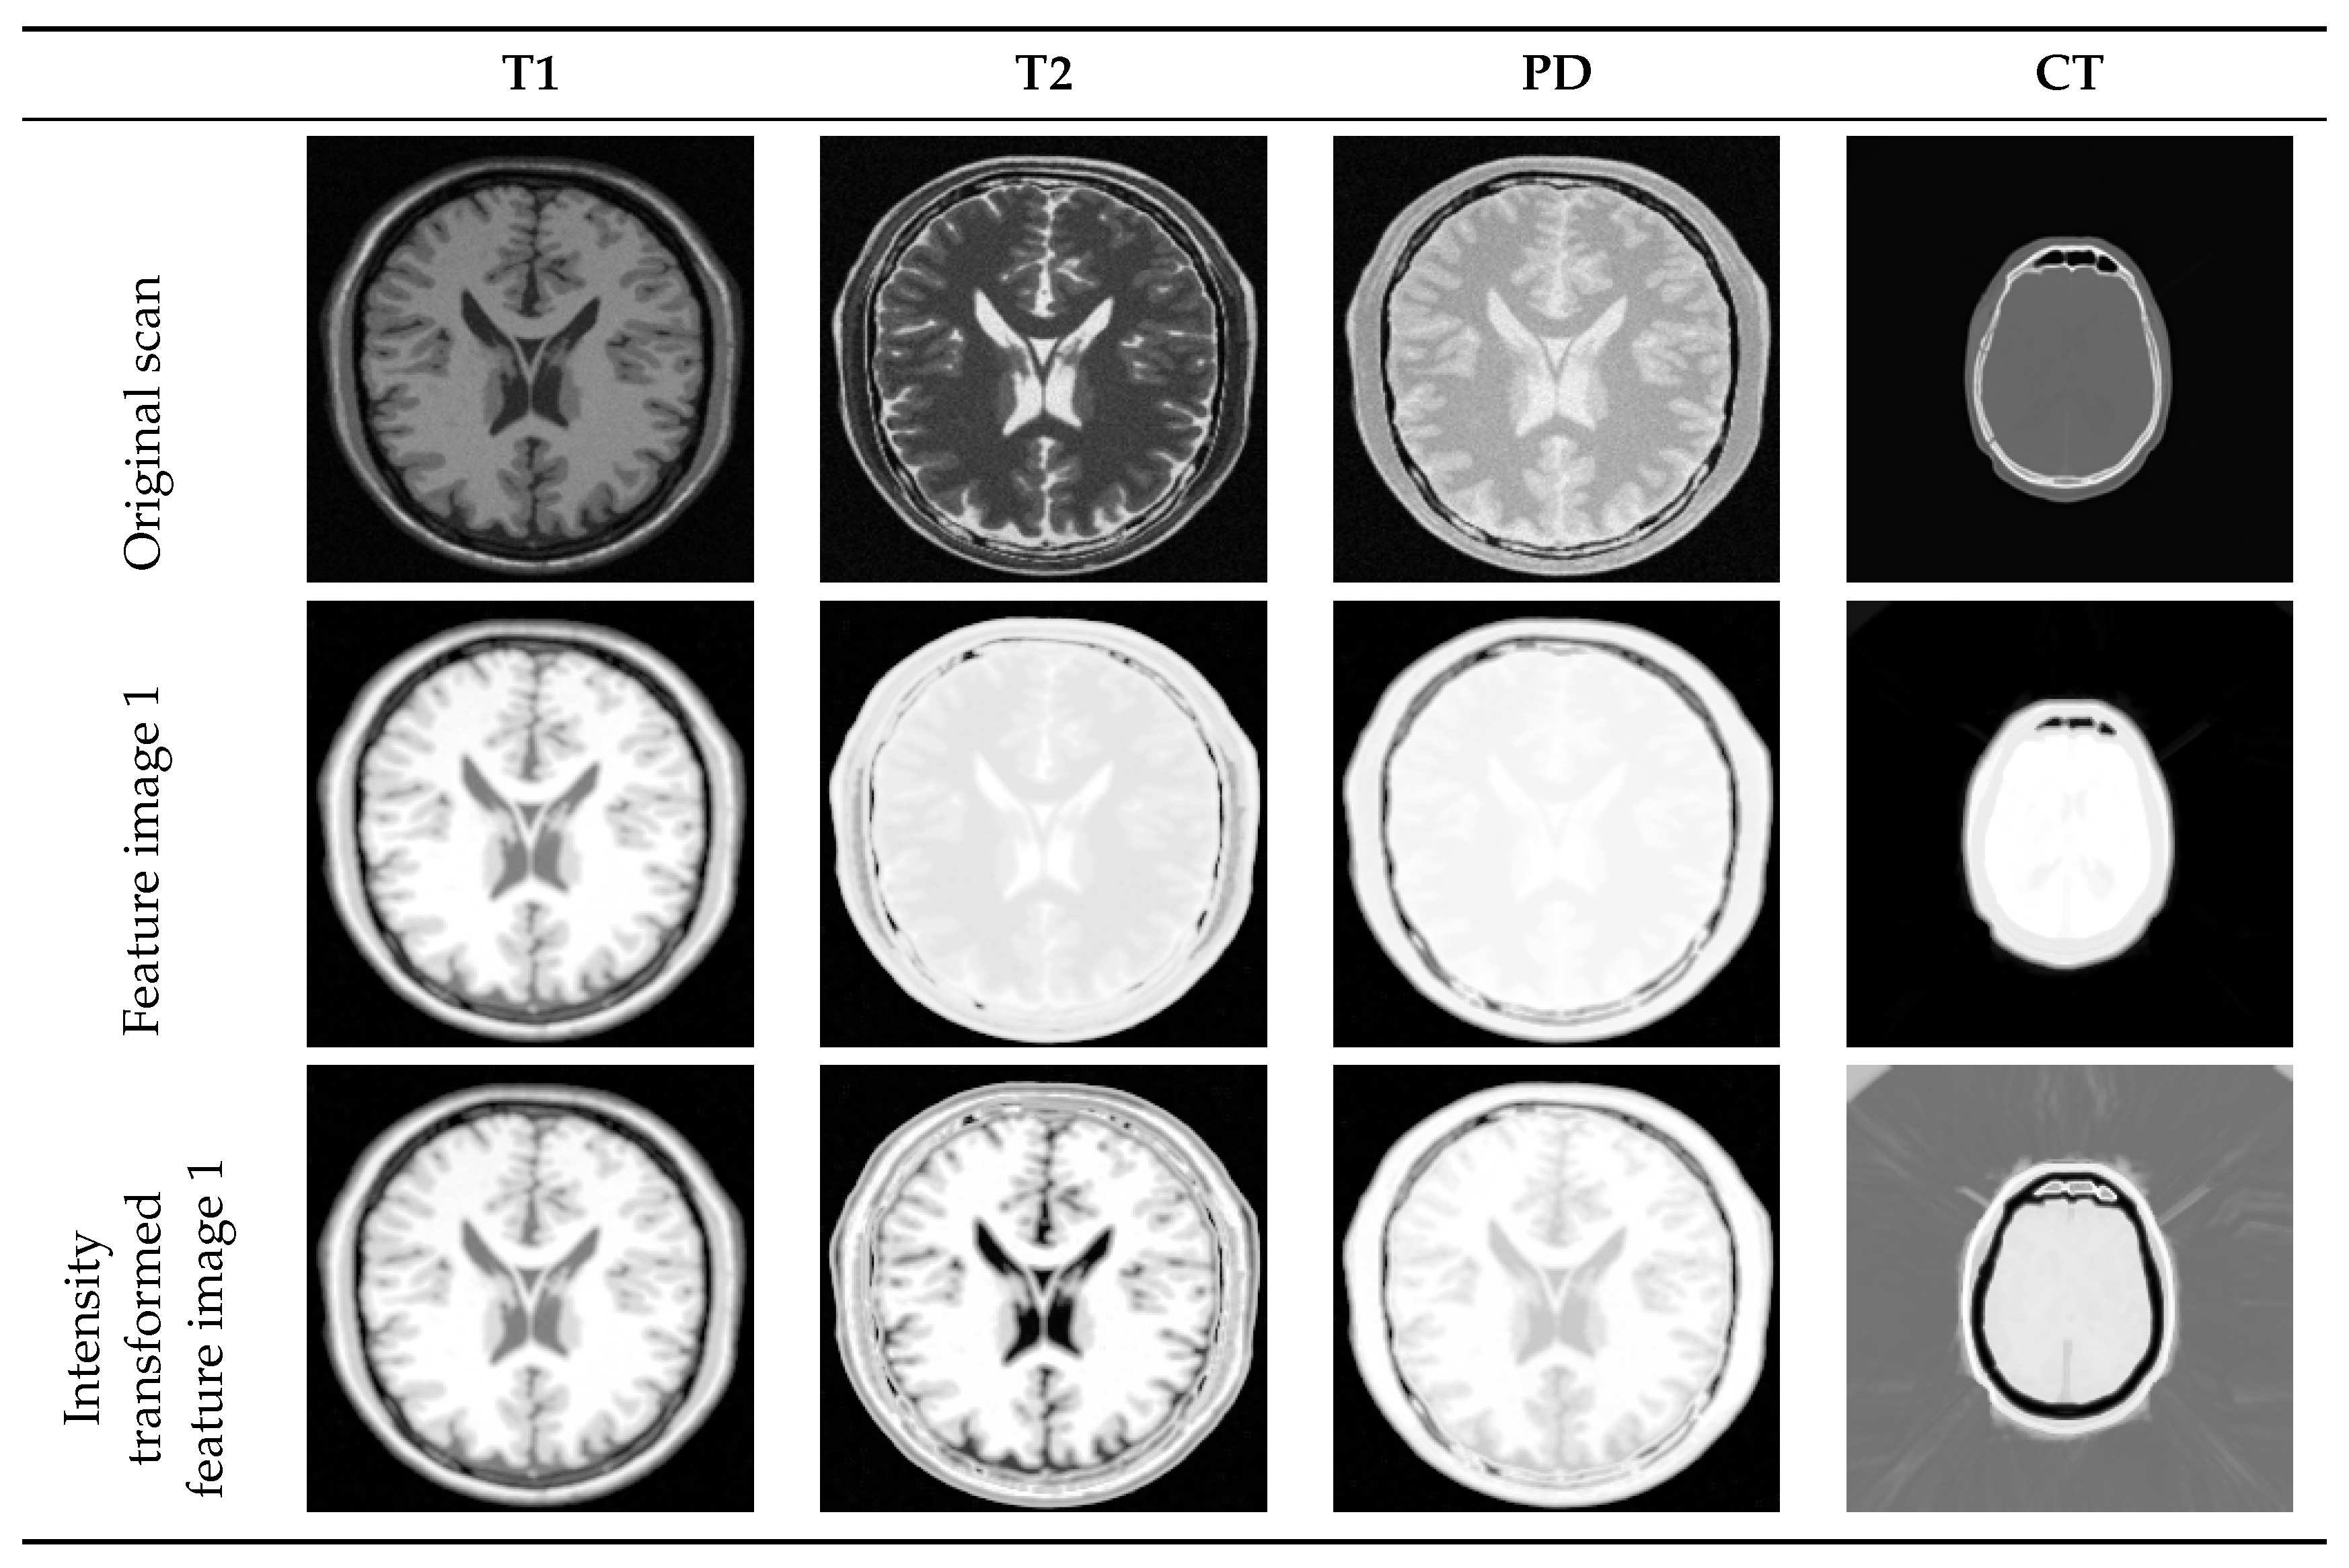

4.2. Multi-Modal to Mono-Modal Transformation

- Wachinger, C.; Navab, N. Entropy and Laplacian images: Structural representations for multi-modal registration. Med. Image Anal. 2012, 16, 1–17. [Google Scholar] [CrossRef] [PubMed]